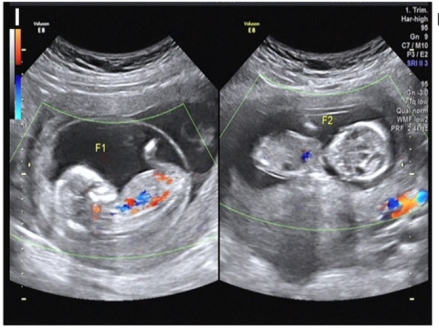

图:46,XX/46,XY嵌合体女性通过辅助生殖技术成功妊娠双胎的影像学图,双胎卵子均为X,其中一个卵子的颗粒细胞100%均为XY核型,一个卵子的颗粒细胞为46,XX/46,XY嵌合体核型

林戈和卢光琇教授,带领团队对一例XX/XY嵌合体的女性进行了详细的研究。该患者曾有过一次妊娠史,后因不孕症寻求辅助生殖技术助孕,其外周血、口腔粘膜、阴道上皮细胞等多种组织均显示其染色体核型为46,XX/46,XY的嵌合体,其中46,XY的比例超过60%。针对为什么患者没有出现男性表型或者两性畸形的表型的科学问题,该团队进行了深入的研究,并发现该患者的外表以及子宫、卵巢、病理切片均为完全正常的女性,在助孕治疗过程中,发现她的卵巢卵母细胞均为XX核型,卵子均为性染色体组成均为X染色体,而颗粒细胞为不同程度的XX/XY嵌合体核型;同时也发现她所有的性别决定与分化的相关基因都没有突变。该夫妇在中信湘雅接受了胚胎植入前遗传学检测(PGT)助孕,并成功怀上了一对双胞胎,值得注意的是其中一个胎儿来自卵泡颗粒细胞染色体100%为XY的卵子。据此,该团队提出了一个新的性别决定理论:人类的性别取决于第5周从卵黄囊经背侧肠系膜迁移而来的原始生殖细胞的性染色体组成,当最初达到性腺嵴的原始生殖细胞性染色体组成为XY时,表现为男性,当性染色体组成为XX时,表现为女性。该患者表现为正常女性,是由于最初达到性腺嵴的原始生殖细胞性染色体组成为XX的结果。